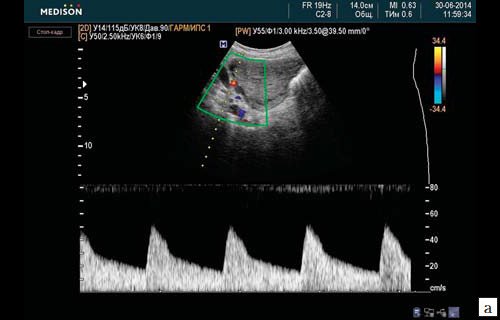

Ультразвуковое исследование кровотока в МА выявило следующие особенности. После перевязки ВПА и ЯА с обеих сторон на фоне акушерских кровотечений в течение первых суток послеоперационного периода кровоток в МА не регистрировался ни в одном из анализируемых случаев (рис. 3). На вторые сутки послеоперационного периода кровоток в МА отмечался у 6,6% пациенток. На третьи сутки кровоток в МА регистрировался у 93,4% пациенток (рис. 4). На пятые сутки гемоциркуляция в МА отмечалась у всех оперированных женщин.

Кровоток в левом сосудистом пучке матки (a. et vena uterine sinistra) не определяется (стрелки).